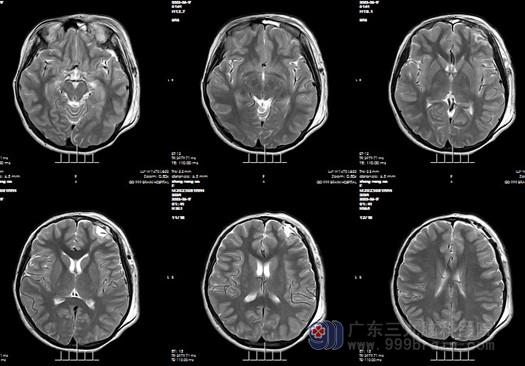

入院后找到了我科的欧阳辉教授,欧阳辉教授和其主治医生看了该患儿的检查片子,为其父母解释道:她的左侧额叶有范围约17×19mm的结节占位病变,考虑低级别神经上皮肿瘤的可能,有明确的手术指征。外十科医生于8月15号为该患儿进行“左侧额叶占位病变切除术”,手术很顺利,病理报告:符合胚胎发育不良性神经上皮肿瘤(DNT)。现在患儿恢复良好,已经出院。

术后影像